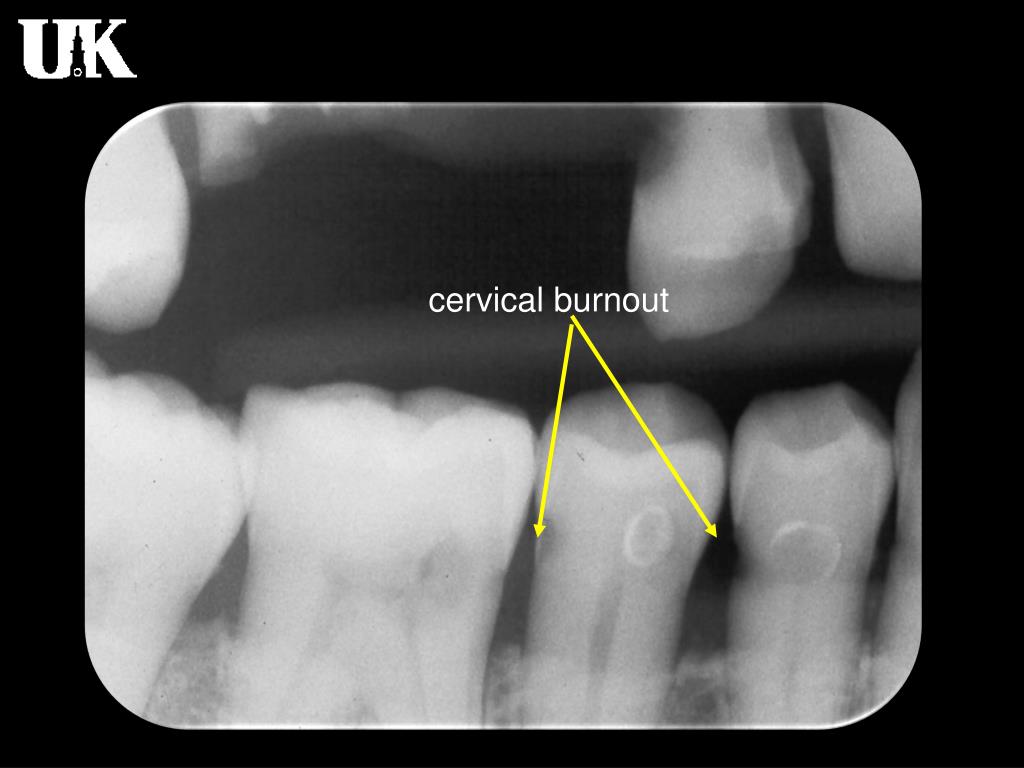

Burnout Dental X Ray . Radiologists are no exception, with up to 46% of. Burnout is an extremely prevalent issue among healthcare professionals. Dentists’ knowledge about the entities mimicking the proximal carious lesion detected by bitewing radiography is important for clinical practice to. , who noted that mach bands and cervical. The relevance of the mach band effect to dental radiology was pointed out by berry jr. Cervical burnout refers to the diffuse relatively radiolucent area on proximal surfaces at the cervical regions between the. Also known as cervical translucency or cervicalucency, cervical burnout appears as a radiolucent band around the necks. Accurate interpretation of dental caries starts with accurate radiograph. Two phenomena (cervical burnout and mach band) create radiolucent areas that can mimic carious lesions.